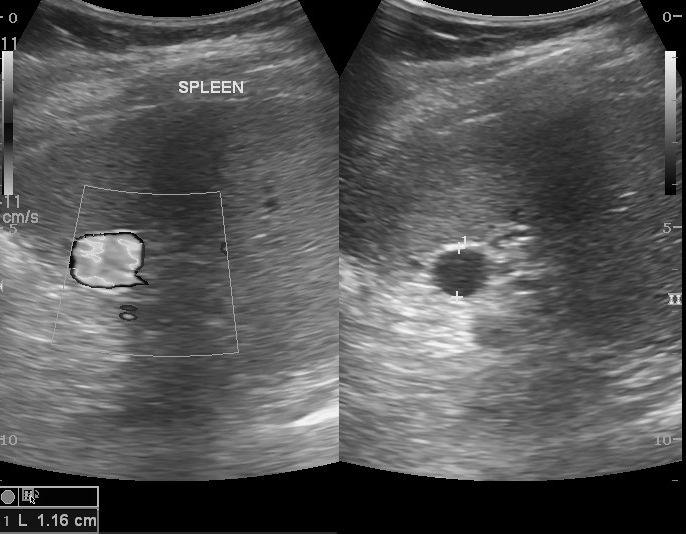

Accessory Spleen

Splenic granulomas

focal lesions resulting from previous infection

Hemangioma

Splenic infarct

common in patients with bacterial endocarditis and splenic artery aneurysms

general abdominal sepsis

Splenic Abscess

Splenic Artery Aneurysm